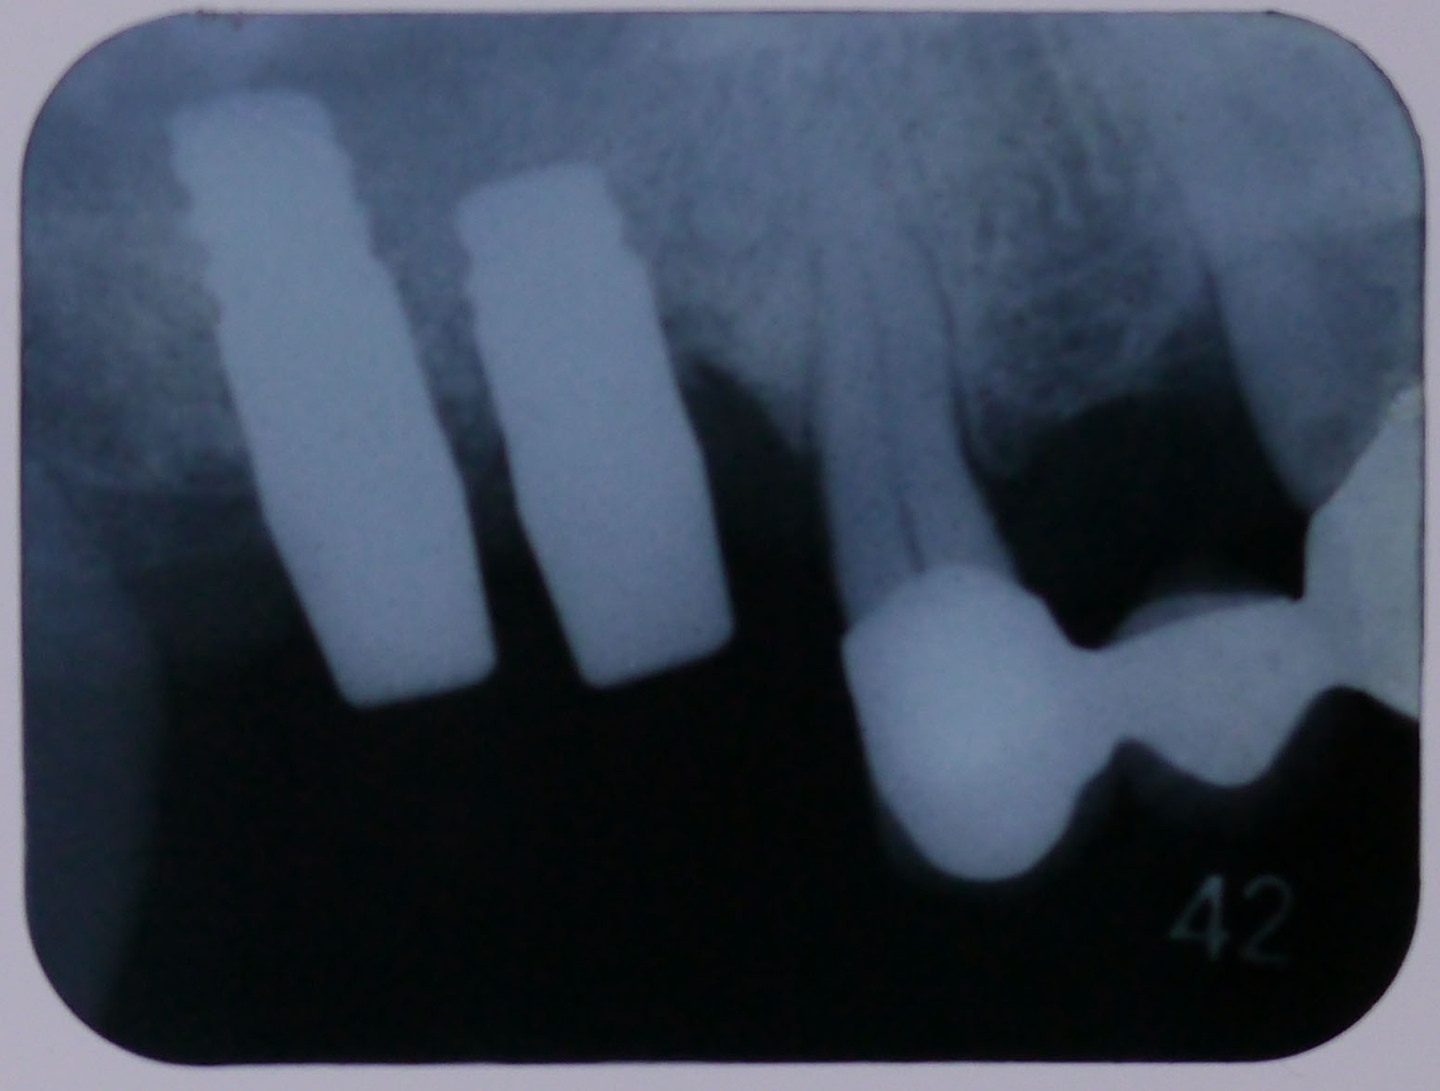

レントゲン画像1

平成24年9月11日の手術後のレントゲン画像

レントゲン画像2

平成25年1月16日、4ヶ月後のレントゲン画像